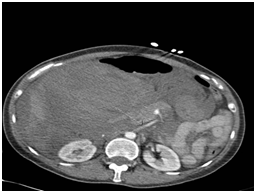

On physical examination there was mild abdominal distension with right sided abdominal tenderness with guarding and present bowel sounds. Blood tests on admission were mildly deranged with white cell count (WCC) of 12.2g/dL neutrophils 10.7%, haemoglobin (Hb) 11.7g/dL, C Reactive Protein<0.6, amylase 28u/L and lactate 0.9mmol/l. Two hours later the patient deteriorated clinically with a fall in BP to 88/50, diaphoresis, Hb dropped to 6.6 g/dL and her lactate rose to 2 mmol/l. The sudden decrease in Hb suggested her deterioration was of haemorrhagic origin. She was transferred to ICU for resuscitation and once she had been stabilised a CT scan was undertaken to determine the source of bleeding. Contrast-enhanced abdominal computed tomography showed a massive intra-abdominal haemorrhage with active extravasations closest to the branches of the superior mesenteric artery especially inferior pancreatic duodenal artery (Figure 1).

Figure 1 Abdominal computer tomography with contrast showing extravasations from inferior pancreatoduodenal artery (arrow).